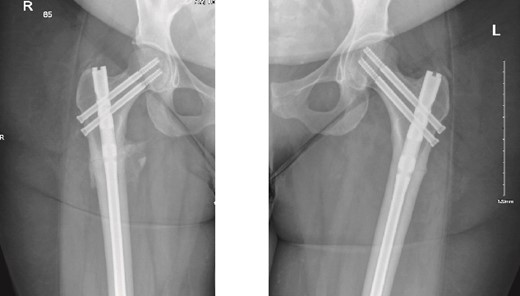

The patient was seen in the clinic at 2 weeks, 6 weeks, and 6 months post-surgery. She was doing well, reporting only mild pain. She was fully weight-bearing with the assistance of a cane and had good range of motion (Figs 3 and 4).

6-months follow-up anteroposterior (AP) view of the right and left femurs after CRIF with IM nail.

As part of the follow-up, the endocrinology team continued to monitor the patient for further investigation into the possible causes of the fractures. A BMD scan was performed and showed normal results. Based on their assessment, the endocrinology team diagnosed the patient with osteomalacia, most likely of nutritional origin.

On the contralateral side, the fracture was a cortical stress line, and a prophylactic nailing was performed. As reported in the literature, the most common approach for incomplete AFFs is surgical fixation, as these fractures are more likely to progress to complete fractures [7]. Previously reported cases managed prophylactically have shown full radiographic union, with patients being pain-free ~8 months post-surgery [8]. In contrast, our patient achieved full clinical union just 2 months postoperatively, mobilizing independently with a cane for support and being pain-free.